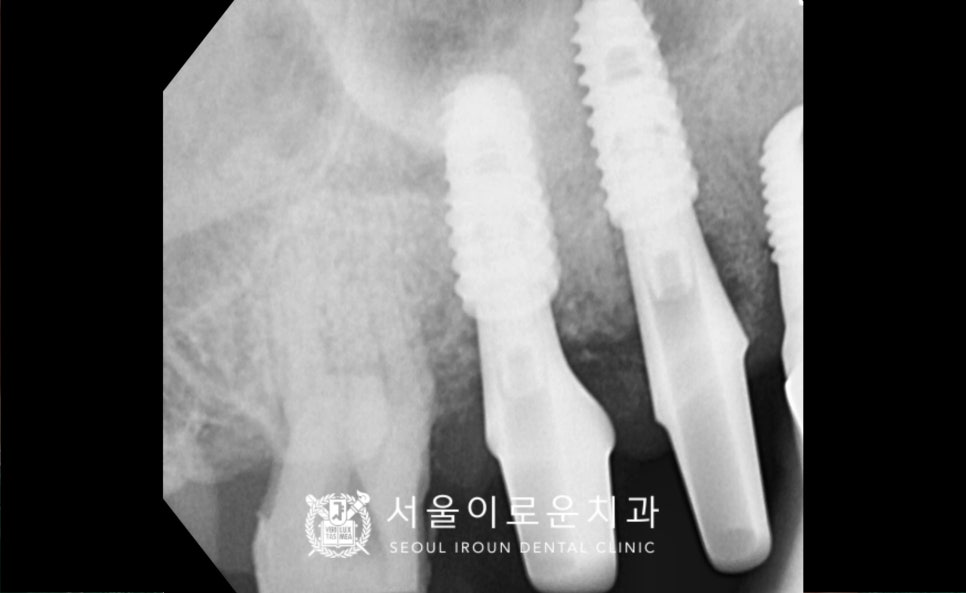

위턱 오른쪽의 임플란트가 잇몸뼈와

단단하게 결합되기를 기다리는 동안

그리고 임플란트 식립 후 4개월 뒤

osstell beacon이라는

골 유착을 확인할 수 있는 장비를 이용하여

isq를 측정하여

뼈와 임플란트가 잘 결합되었는지

안정 값을 확인한 뒤

보철 과정을 진행하였답니다.

그리고 맞춤형 지대주를 체결하여

자연치아와 강도가 가장 유사하고

심미적인 지르코니아 크라운으로

임플란트 보철물과 크라운 보철물을

마무리해 드렸습니다.